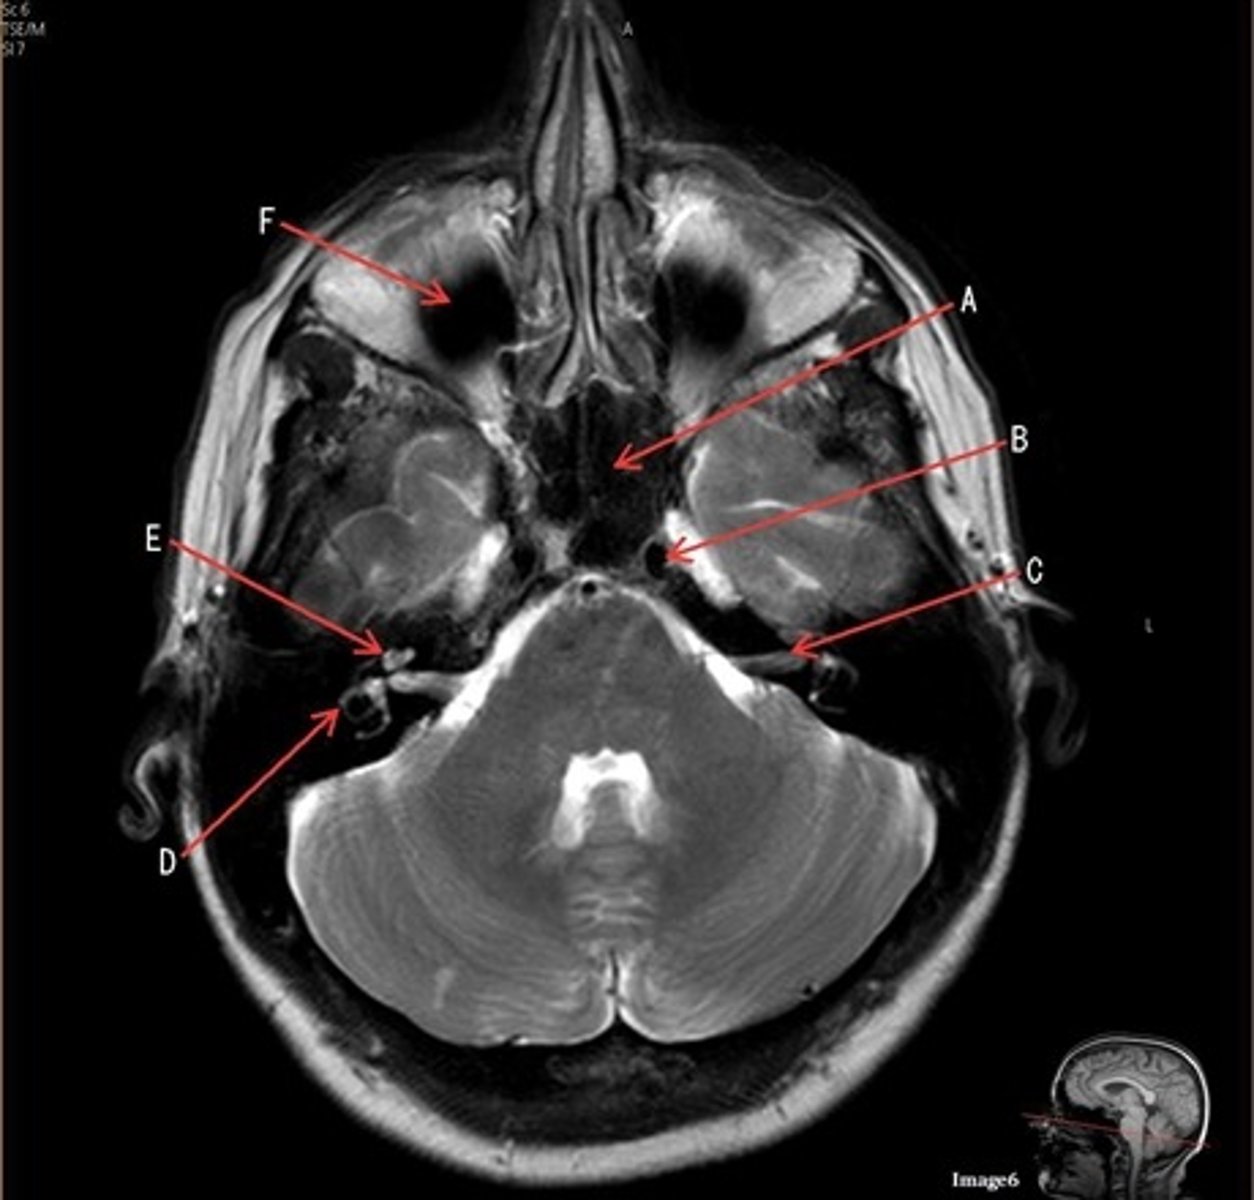

A

A- anterior cerebral artery

C

C- 7th cranial nerve, facial nerve

D

D. semi-circular canal

E

E- cochlea

F

F- maxillary sinus

Which arteries join together to form the basilar artery?

vertebral arteries

letter A

anterior cerebral artery

letter C

7th cranial nerve- facial

8th cranial nerve vestibulocochlear on other side (posterior) of semicircular canal